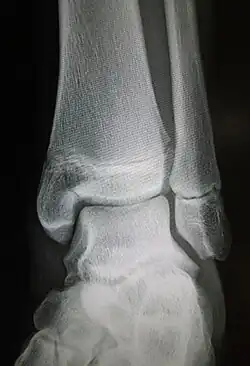

| Radiograph showing a Maisonneuve fracture of the proximal fibula | |

The Maisonneuve fracture is a spiral fracture of the proximal third of the fibula associated with a tear of the distal tibiofibular syndesmosis and the interosseous membrane. There is an associated fracture of the medial malleolus or rupture of the deep deltoid ligament of the ankle. This type of injury can be difficult to detect.[1][2]